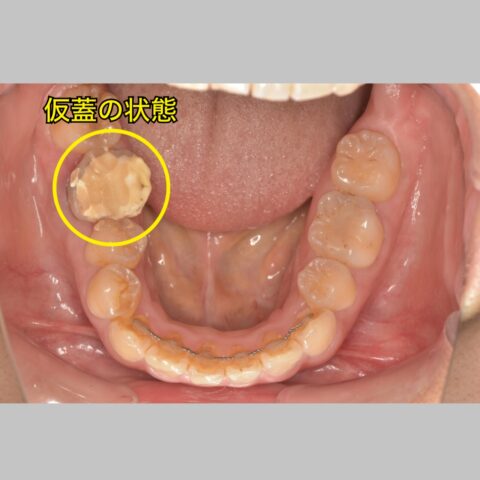

あともう一つ起きているトラブルは

仮蓋のセメントが歯肉の下まで入っています…

🟰フェルールがない

(残っている歯が歯肉の下までしかない)

ということです。